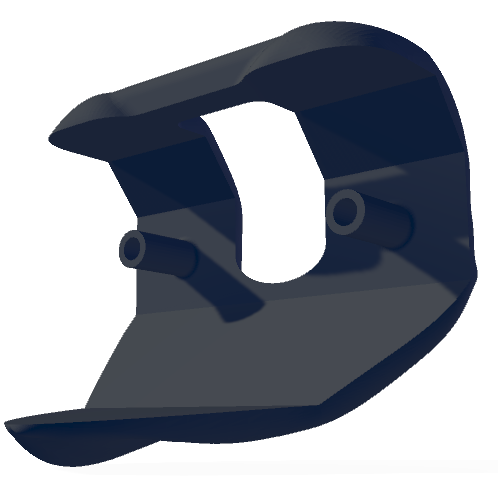

2.2 Data acquisition and implant design

The study included two femoral and five tibial radiopaque implant designs manufactured from aluminium to mimic widely used geometries (Fig. 3). The implant geometries were adapted from CAD models provided by Zimmer Biomet (Winterthur, Switzerland) by smoothing all intricate geometries and adjusting non-load support wings while retaining the overall topology. A total of ten femur-tibia implant combinations were tested, with each combination following kinematic trajectories derived from the CAMS-Knee datasets [18, 2]. The implant poses for each time instant replicated the complete trials of various activities.

Figure 3: Comparison of different tibial and femoral implant designs: (a) Asymmetric round wings with fixed bearing, (b) Asymmetric straight wings with fixed bearing, (c) Symmetric round wings with fixed bearing, (d) Symmetric round wings with mobile bearing, (e) Femur crossbar design, (f) Femur normal design, (g) Asymmetric no-wings with fixed bearing.